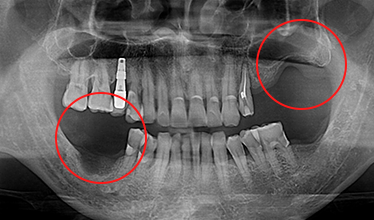

CASE 02

-

임플란트 식립 전 -

임플란트 식립 후 -

임플란트 보철 후